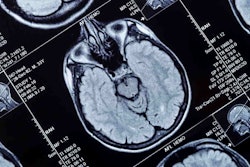

Artificial intelligence (AI) software developer Subtle Medical has added imaging center operator Halo Diagnostics to its customer list.

Subtle has installed its SubtleMR and SubtlePET AI-based image enhancement software at multiple Halo locations, according to the company.